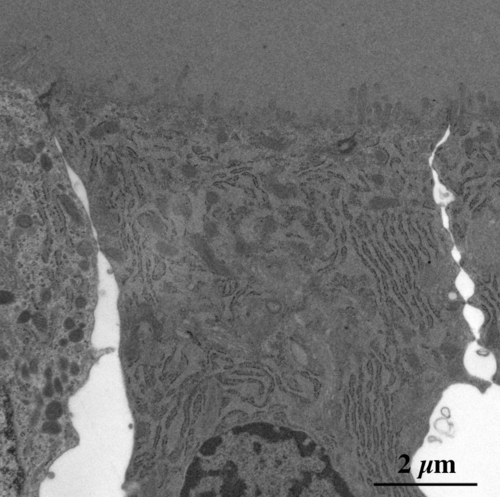

【 薄さ70 - 80 nm 超薄切片の透過型電子顕微鏡画像 】

Transmission electron microscopic image of 70 - 80 nm ultrathin section

濾胞上皮細胞 follicle epithelial cells

濾胞上皮細胞頂上部の拡大像